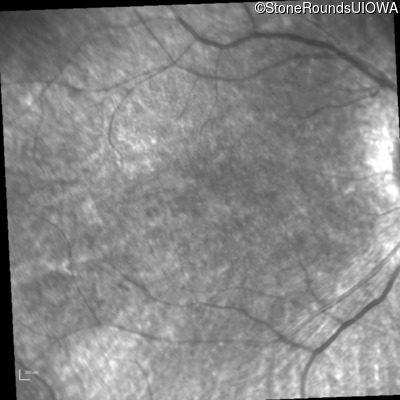

Infrared Fundus Photograph - Left - 20/80

Exemplar